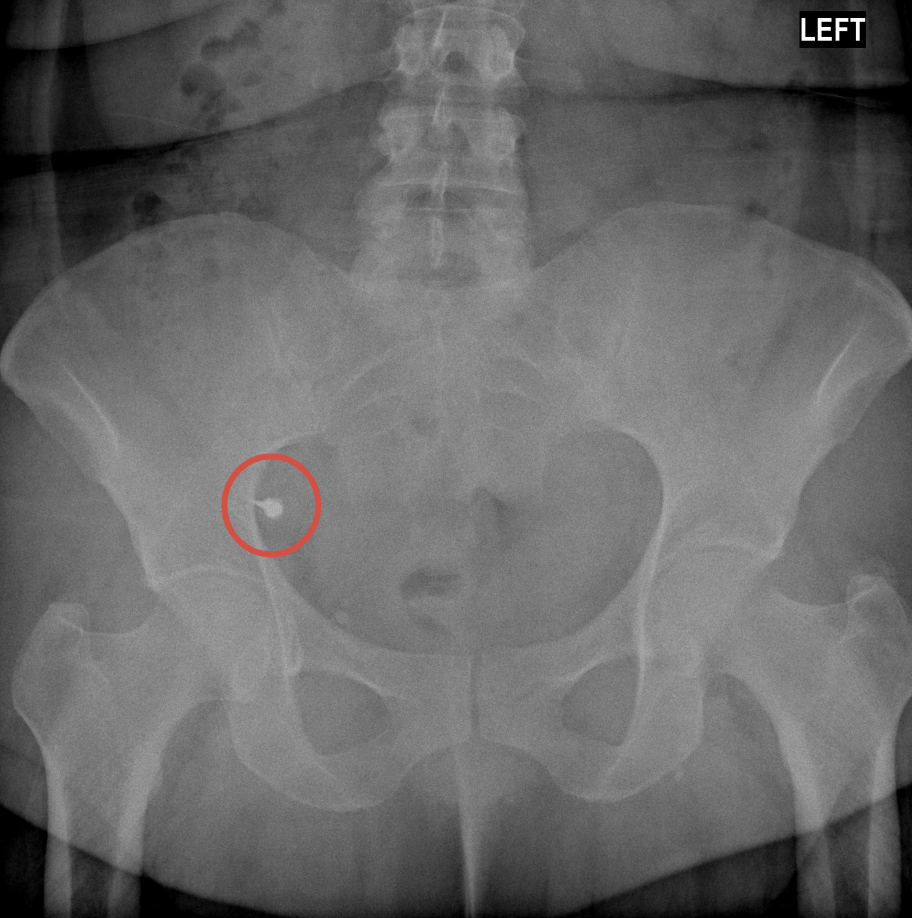

Иллюстрации к случаю:

2. Рентген органов брюшной полости через сутки — инородное тело в правой подвздошной кишке.